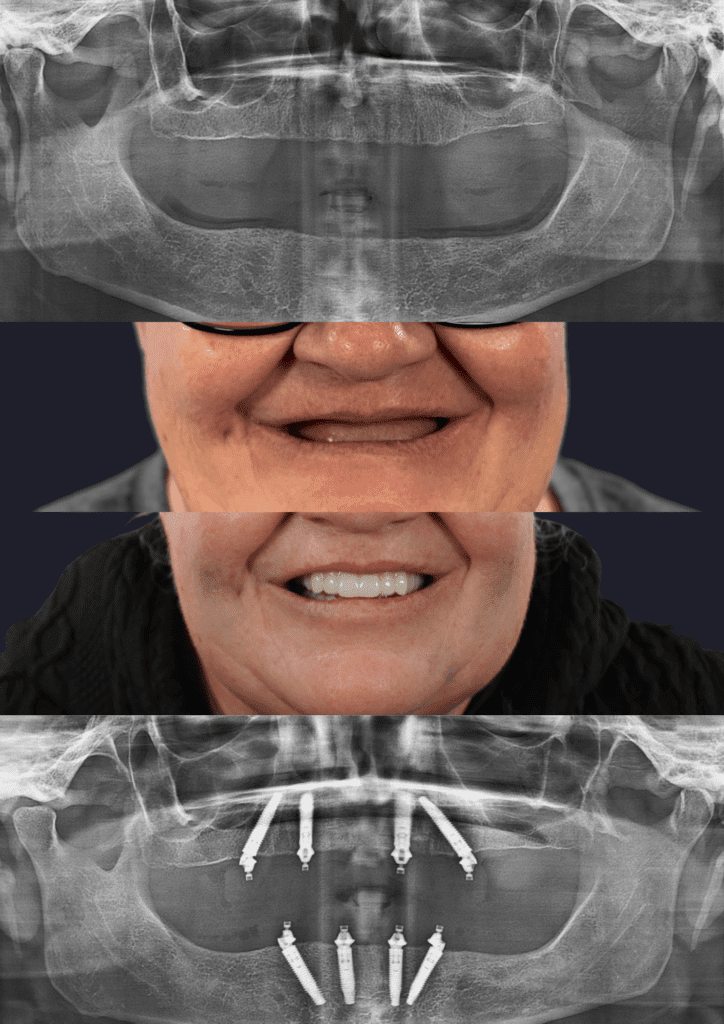

Before & After Treatment Gallery

The photos shown here document completed full-jaw implant treatments. Each case involved detailed planning, surgical placement of implants, and a custom-made fixed bridge. Treatment outcomes, timelines, and suitability vary and are assessed on a case-by-case basis.